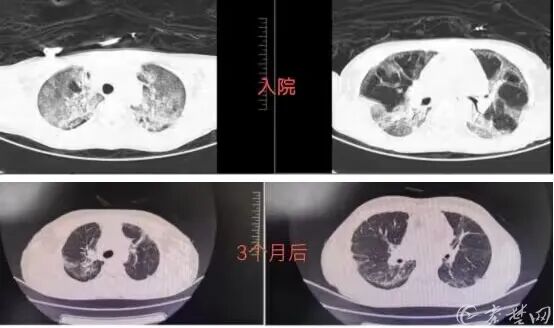

小黄(化姓)家住河南省某县,今年4月19日,他口服百草枯约100ml。被家属发现后,就及时送至当地医院行洗胃、血液灌流等支持治疗。然而,抢救治疗的效果并不好,随后他还出现了呼吸困难进行性加重的情况,CT也显示为“大白肺”。当地医生表示孩子的情况极不乐观,恐难治愈。

事发一周后,在当地医院救护车的护送下,小黄被送至十堰市人民医院急诊科。刚入院时,他已出现严重呼吸困难、“大白肺”等症状,情况十分危急。根据以往经验及相关文献报道,百草枯的成人致死量为5~15 ml(20%的浓度),口服量大于40ml百草枯水溶液属于爆发型中毒患者,多在1天内出现肺水肿,常在数小时至数天内死于急性呼吸窘迫综合征或多器官功能衰竭,临床存活率极低。小黄口服高达100ml百草枯,短时间内快速进展为重度急性呼吸窘迫综合征(ARDS),从理论和经验上看,该例患者不可能存活。

结合丰富的临床救治经验,根据患者实际情况,李虎年团队综合评估病情,紧急制定了抢救方案进行抢救,同时采用专家共识方案,2小时内实现上机血液灌流+血液滤过,从胃肠功能保护到延缓肺纤维化,从积极排毒到预防肝肾损害,维持机体电解质、酸碱平衡,护理口腔喉咽部粘膜溃疡,每项治疗都环环相扣,并逐日调整药物用量。经过坚持不懈的努力,患者的氧合逐渐上升,1周后复查肺部CT病灶开始吸收,1个月后患者便康复出院。

办理出院时,李虎年还是担心患者肺部病变会反弹甚至肺纤维化,出院谈话时再三叮嘱小黄家属要定期复查,出现病情变化及时联系。由于路途遥远,孩子家属选择在当地某综合性医院定期复查,同时每次都会把片子发给李虎年查看并请他指导康复。在李主任指导下,小黄肺部病变进一步吸收,康复良好。